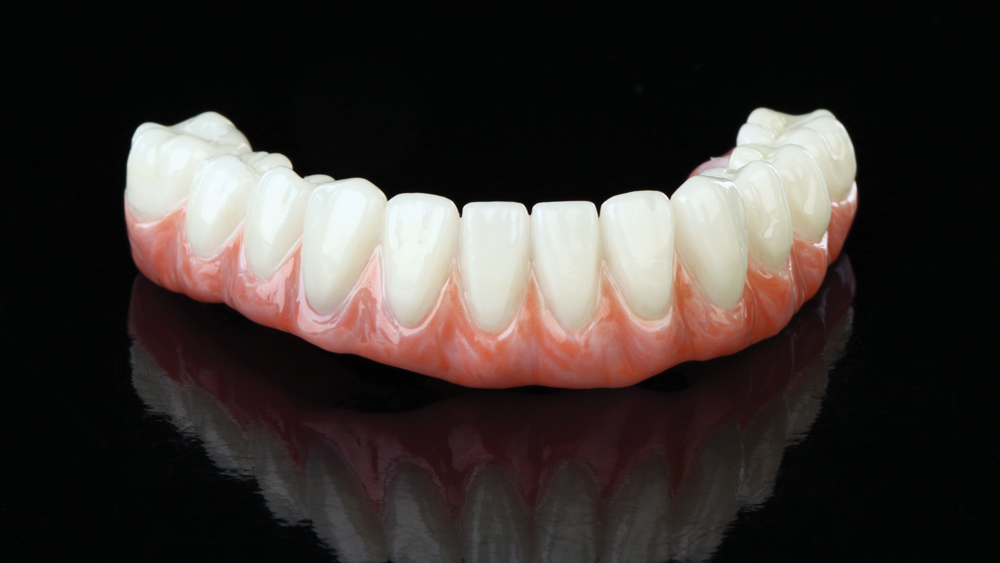

Once osseointegration is complete, the BruxZir® Full-Arch Implant Prosthesis is the ideal choice for the restoration, as its monolithic construction prevents chips, stains, breakage, and dislodged or worn-down prosthetic teeth.3,4 This treatment option has helped elevate the quality of care I’m able to provide for my edentulous patients, who no longer return to my office with a broken acrylic appliance in hand.